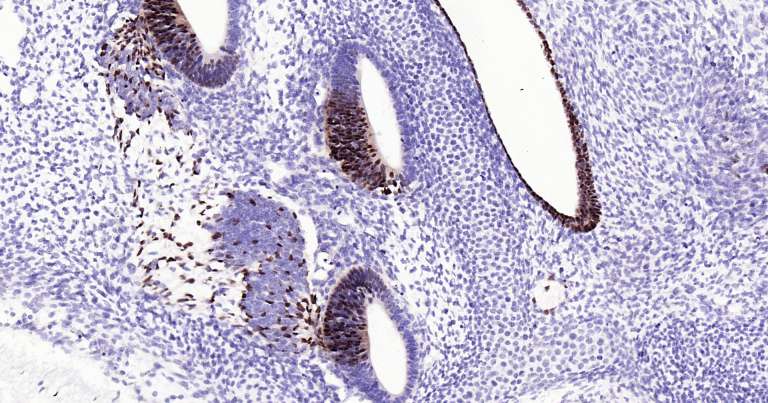

Immunohistochemical analysis of paraffin embedded mouse embryo tissue slide using IHC0210M (Mouse SOX2 IHC Kit).